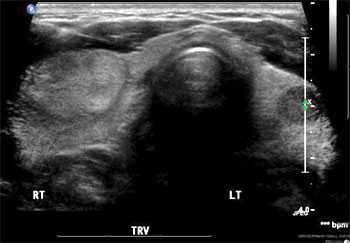

Thyroid Nodule

thyroid nodule Solid or fluid-filled lumps that grow in the thyroid gland are called nodules. More than 90 percent of thyroid nodules are benign (noncancerous).

These growths are common and affect about half of people aged 60 or older. Women are more likely than men to develop thyroid nodules. If you suspect you have a thyroid nodule, turn to the thyroid experts at Henry Ford Health System for an accurate diagnosis and effective treatment.